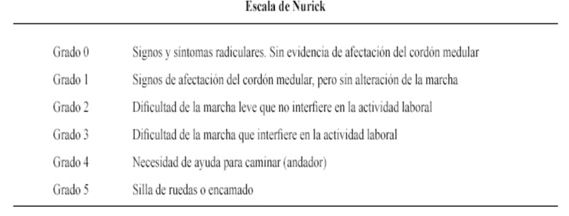

Se analizó el JOA y Nurick pre y post operatorio. La mejoría neurológica la valoramos calculando la tasa de recuperación del JOA. Esta se calcula: JOA postoperatorio - JOA preoperatorio/ JOA máx. (17)- JOA preoperatorio X 100 (Tabla 1 y Tabla 2).

De estos, 58 pacientes (69 %) son masculinos. La media de edad fue de 63 años (rango 35-89). El tiempo de inicio de sintomatología hasta la cirugía fue variable, siendo menor a 12 meses en 54 casos (64%). En total se intervino 254 niveles. El nivel más frecuente fue C3-C6, en 210 oportunidades (83%), seguido de C3-C7 en el 7 %. En ningún caso se registró alteración de los potenciales motores sensitivos. En 30 casos se usó injerto autólogo de cresta iliaca. No tuvimos lesión de duramadre ni agravamiento de la sintomatología clínica, Tampoco infecciones profundas. Ningún paciente requirió revisión ni se registró cierre de la osteotomía. Dos pacientes presentaron parálisis transitoria de C5 posoperatoria. En ambos casos la sintomatología revirtió completamente al cabo de 5 meses. Un paciente presento seroma que requirió drenaje. Un caso presento infección superficial que fue tratada satisfactoriamente con antibióticos vía oral. En 4 pacientes de registro dolor axial leve posoperatorio sin tenerlo previamente. La media del JOA pre y post operatorio a 6 meses fue de 12,1 y 14,8 respectivamente, una tasa de recuperación promedio de 81%. La tasa de recuperación en pacientes intervenidos antes del año fue de 83 % y de los intervenidos más de un año de inicio de sintomatología de 73%. El Nurick pre operatorio promedio fue de 2 y postoperatorio a los los 6 meses de 1,1.

Las complicaciones globales fueron algo menores a las descriptas en la literatura5)(6. La incidencia de parálisis de la raíz C5 se encuentra en el límite inferior de con respecto a las reportado en grandes series, siendo en nuestro caso 5% (2 casos). Esta lesión se debe a la disposición anatómica de la raíz C5 la cual emerge de manera más horizontal por lo cual es más sensible a las tracción o a las fuerzas que se le aplica a diferencias del resto de las raíces cervical, dicha lesión pasa desapercibida en muchos casos, de todas maneras destacamos que en todos los casos correspondió a neuropraxias siendo lesiones reversibles. 4 presentaron dolor axial que no tenían previo a la cirugía, creemos dicho dolor se puede deber a sobre distensión facetaria o debido a alteraciones del balance sagital. La tasa de recuperación del JOA (modificado dado que en nuestra cultura no se utilizan alguno de los elementos que describen en el JOA original) es de 81 % siendo mayor en aquellos intervenidos antes del año de la sintomatología. Si bien estos valores son comparables a lo publicado en las series7)(8 creemos que la el JOA post operatorio así coma la tasa de recuperación no es mayor ya que la mayoría de los pacientes intervenidos presentan una mielopatía leve, y casi la mitad fue intervenida antes del años de iniciado los síntomas. El Nurick post operatorio mostró una mejoría significativa pasando 2.1 pre operatorio a 1,1 post operatorio a los 6 meses. En los pacientes con alteración de señal medular (40%) presentaban tasa de recuperación del JOA mayor comparación con los que no tenían. Por otro lado, no vimos cambios con respecto al Nurick.

Si bien la escala de Nurick tiene las limitantes que no toma en cuenta los miembros superiores, pensamos que fue una escala apropiada para el presente estudio, ya que permitío ilustrar la mejoría obtenida en nuestros pacientes.